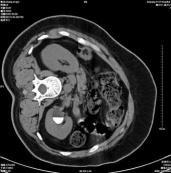

肾钙乳(calcium milk of the kidney)是指肾盏憩室内含钙微粒组成的混悬液,实际上是一种特殊类型的尿石症。由于重力的关系,钙乳微粒的位置随体位的改变而有变化,其形成与尿路梗阻、尿液浓缩、慢性炎症有关。分为两种类型:①囊肿型,多在肾上盏;②积水型,肾下盏多见。